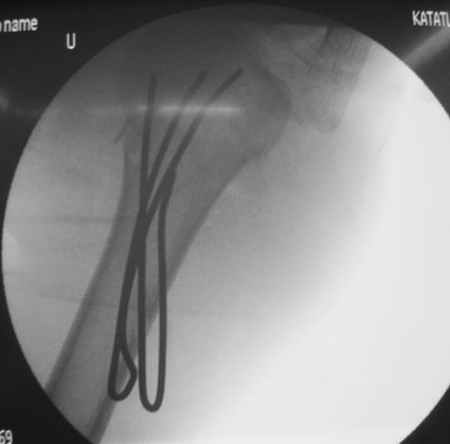

Коллеги, Больной прооперирован вчера. 19 летний пациент с переломом шейки плеча. Закрытая репозиция и чрескожная фиксация спицами под контролем ЭОПа ( техника проф. Лазарева)

Интраоперационный контроль на стабильность фиксации - сомнений в стабильности фиксации не возникло. Послеоперационный контроль сегодня......

Необходимость послеоперационного Рг контроля..... Больной запланирован на повторную манипуляцию и транспозицию спиц Евгений И Чекашкин